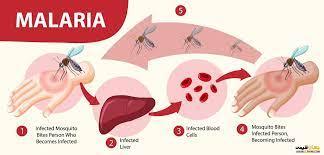

قیمت: 32٬000 تومان - دسته بندی فایل: پاورپوینتپاورپوینت اپیدمیولوژی مالاریا

فروش ویژه پاورپوینت حرفه ای اپیدمیولوژی مالاریاباتخفیف استثنایی -تعداداسلاید.18اسلایدکامل